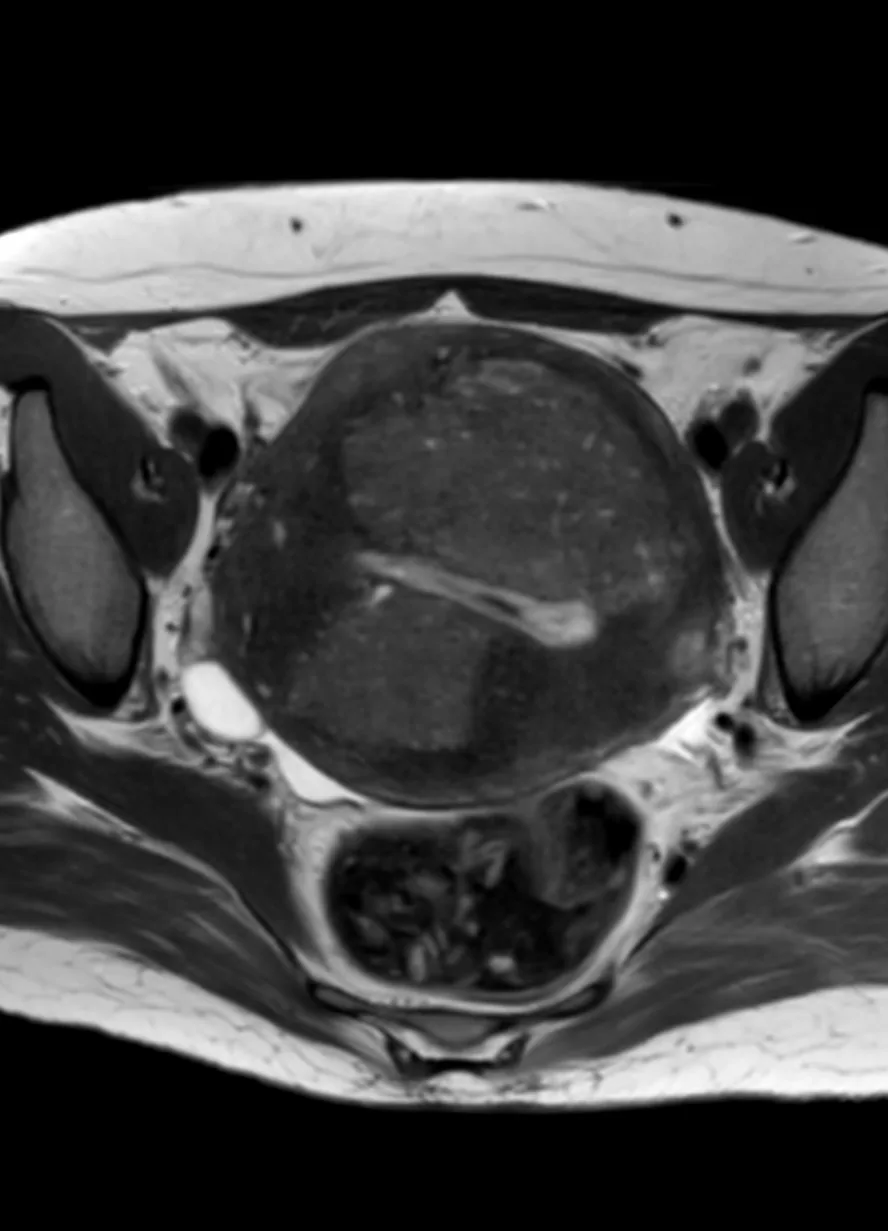

Классные тератомы. 30 лет.

В ОРАЦ есть интересный момент: когда речь о тератоме, то надо оценить, есть ли значительное количество ткани, накапливающей контраст. Субъективная вещь. Один сочтёт, что значительное, другой сочтёт, что не значительное. Но в первом случае это будет четвёртая категория и опухоли надо удалять, а во втором случае это будет вторая категория, и можно просто спокойно понаблюдать. Только что переубедил коллегу написать двойку вместо четвёрки по этим картинкам.

Кривую показываю на всякий случай, она на присвоение категории в данном случае не влияет, но дополнительно успокаивает, что ли. А зубчатость её объясняется тем, что исходные изображения и изображения после субтракции представляют собой одну серию, а вручную их разделять мне было лень. На информативность кривой это никак не влияет.

Видно, что в миометрии контраст накапливается гораздо быстрее и гораздо сильнее. То есть, если бы это на что-то влияло, то эту кривую надо было бы расценить, как кривую низкого риска.